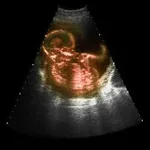

Flere barnløse har afbrudt fertilitetsbehandling, fordi de ikke har råd, efter at der den 1. januar blev indført brugerbetaling.

Barnløse skal nu selv betale en

del af deres fertilitetsbehandling.